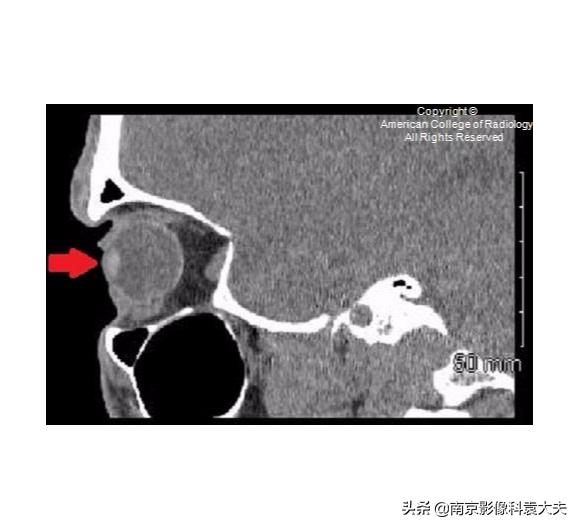

右眼矢状位非对比增强CT(平扫)显示前房(箭头)塌陷。这可以在角膜裂伤的情况下看到。